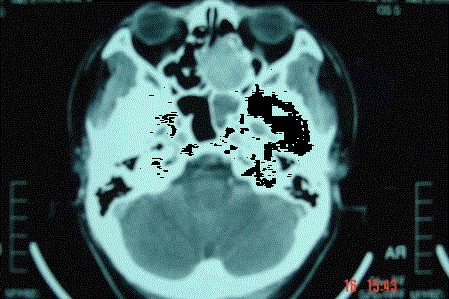

问题 病历摘要: 患者男,37岁,因右鼻塞伴涕中带血4个月入院,患者4个月前始右鼻塞,为间断性,偶有涕中带血,时有流脓性分泌物,并症状渐渐加重。但发病以来患者无头痛、面部麻木和疼痛,无复视及流泪,张口正常。检查:右侧鼻腔总鼻道可见表面光滑、质中、粉红色肿物,触之不易出血。鼻咽黏膜光滑,未见新生物和黏膜糜烂。颈部未及淋巴结肿大。 为了确诊,需做哪些辅助检查?

选项 A、鼻腔鼻窦内窥镜检查 B、生化检查 C、胸正位片 D、鼻窦CT E、鼻窦MR F、鼻咽MR G、胸部CT H、鼻咽CT

答案 ADE